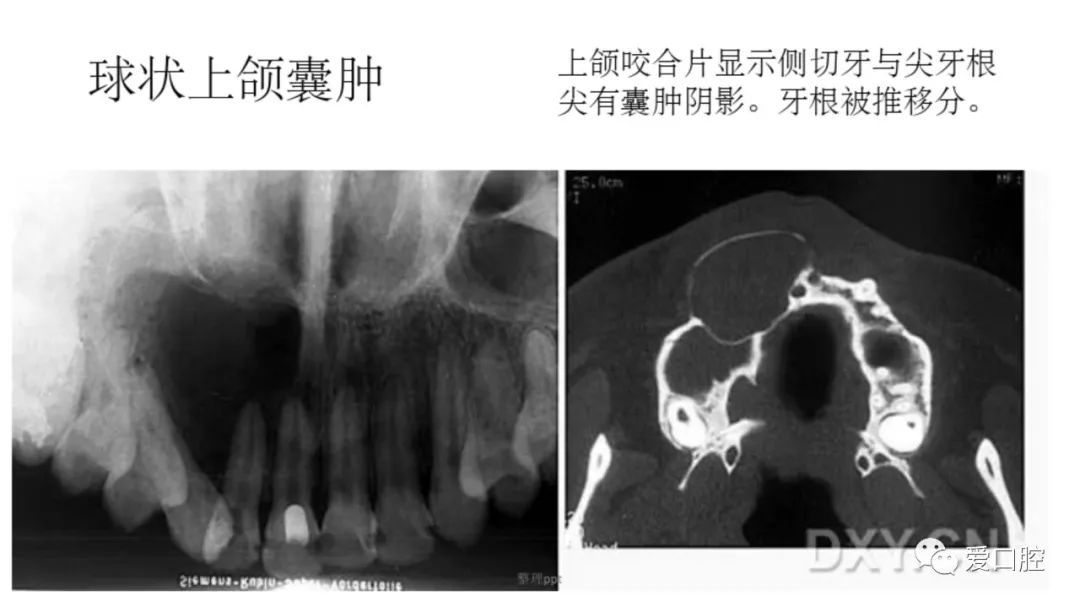

口腔小技巧 | 口腔科常见的病例影像!